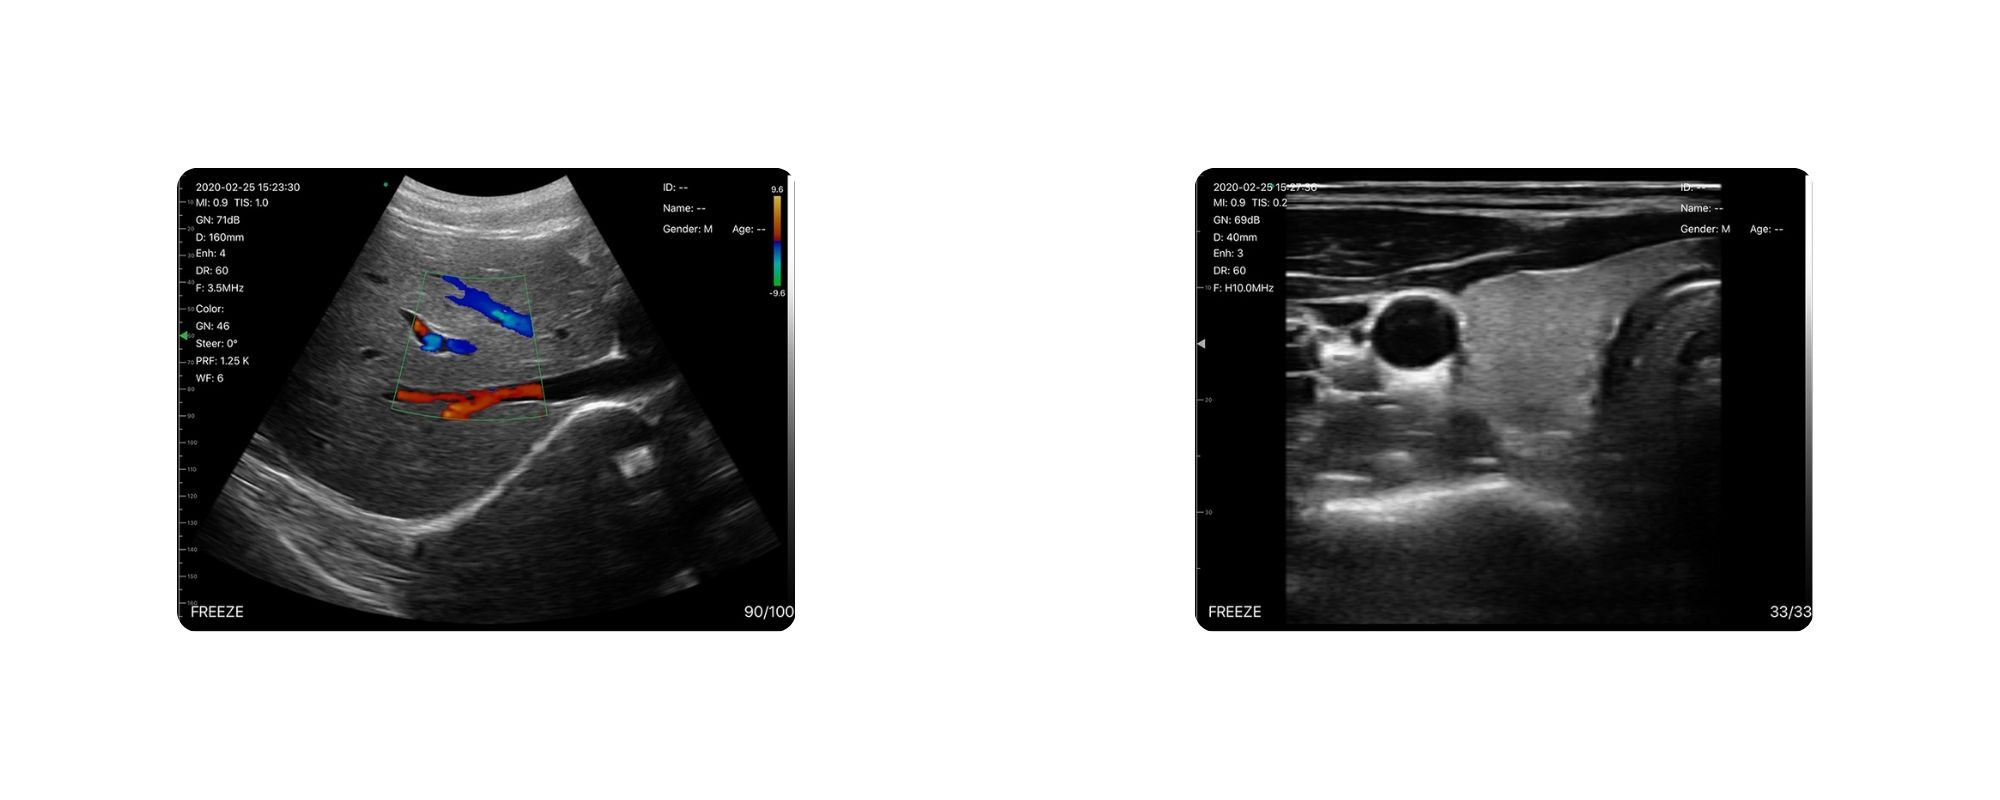

پشتیبانی از تمام مدهای تصویربرداری حرفهای

این پروب تقریباً تمامی مدهای تصویربرداری مورد نیاز در پزشکی را پشتیبانی میکند:

- B Mode – تصویر سیاه و سفید

- B/M Mode – بررسی حرکت و خطوط

- Color Doppler – نمایش جریان خون

- Pulse Wave Doppler – شنیدن صدای جریان یا صدای قلب جنین

- PDI – داپلر قدرت برای عروق ریز

این مجموعه کامل باعث میشود C5LC نهتنها برای معاینات روزمره، بلکه برای تشخیصهای تخصصیتر مانند بررسی عروق، بارداری، حرکات قلب جنین و بافتهای سطحی نیز عملکرد مناسبی داشته باشد.

دو سر کانوکس + لینیر در یک دستگاه 250 گرمی

همانطور که پیشتر گفته شد؛ پروب C5LC دارای دو سری کانوکس و لینیر است که آن را به ابزار چندمنظوره تبدیل میکند:

کانوکس (3.5 – 5 MHz)

- مناسب برای اسکنهای عمقی

- ارگانهای شکمی، کلیه، کبد، مثانه، طحال

- تشخیص بارداری

لینیر (7.5 – 10 MHz)

- مناسب برای سطحیترین و دقیقترین تصاویر

- بافت نرم، عضلات، MSK، عروق سطحی، گرههای لنفاوی

وزن فقط 250 گرم این پروب، آن را برای کاربردهای سیار، اورژانسی و دامپزشکی بسیار محبوب کرده است.